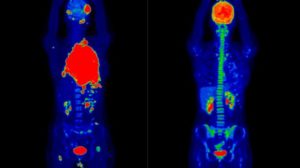

Высокие уровни инсулина вследствие недавнего употребления углеводистой пищи, либо после его экзогенного введения, могут привести к значительному захвату изотопа мышечной тканью, что ухудшает качество исследования (Рисунок 1).

Пациенту следует избегать повышенной физической нагрузки за день до исследования, а после инъекции ФДГ следует расслабиться, прекратить разговаривать, жевать, необходимо избегать гипервентиляции – для того, чтобы минимизировать физиологический захват 18-ФДГ мышечной тканью.

На данном снимке видны метастазы опухоли в печень, визуализируются даже небольшие по размерам узлы на периферии.